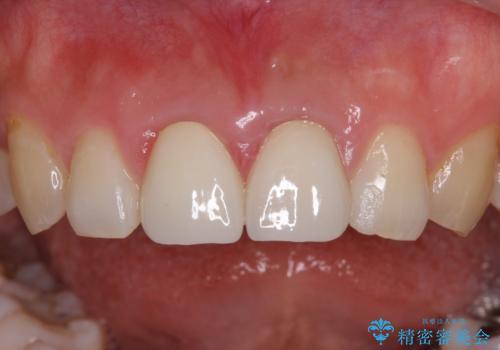

下顎前歯の部分矯正に半年ほどかかってしまい、少し期間は長いものとなりましたが、上下ともに前歯がきれいに整い、患者様には大変満足していただきました。